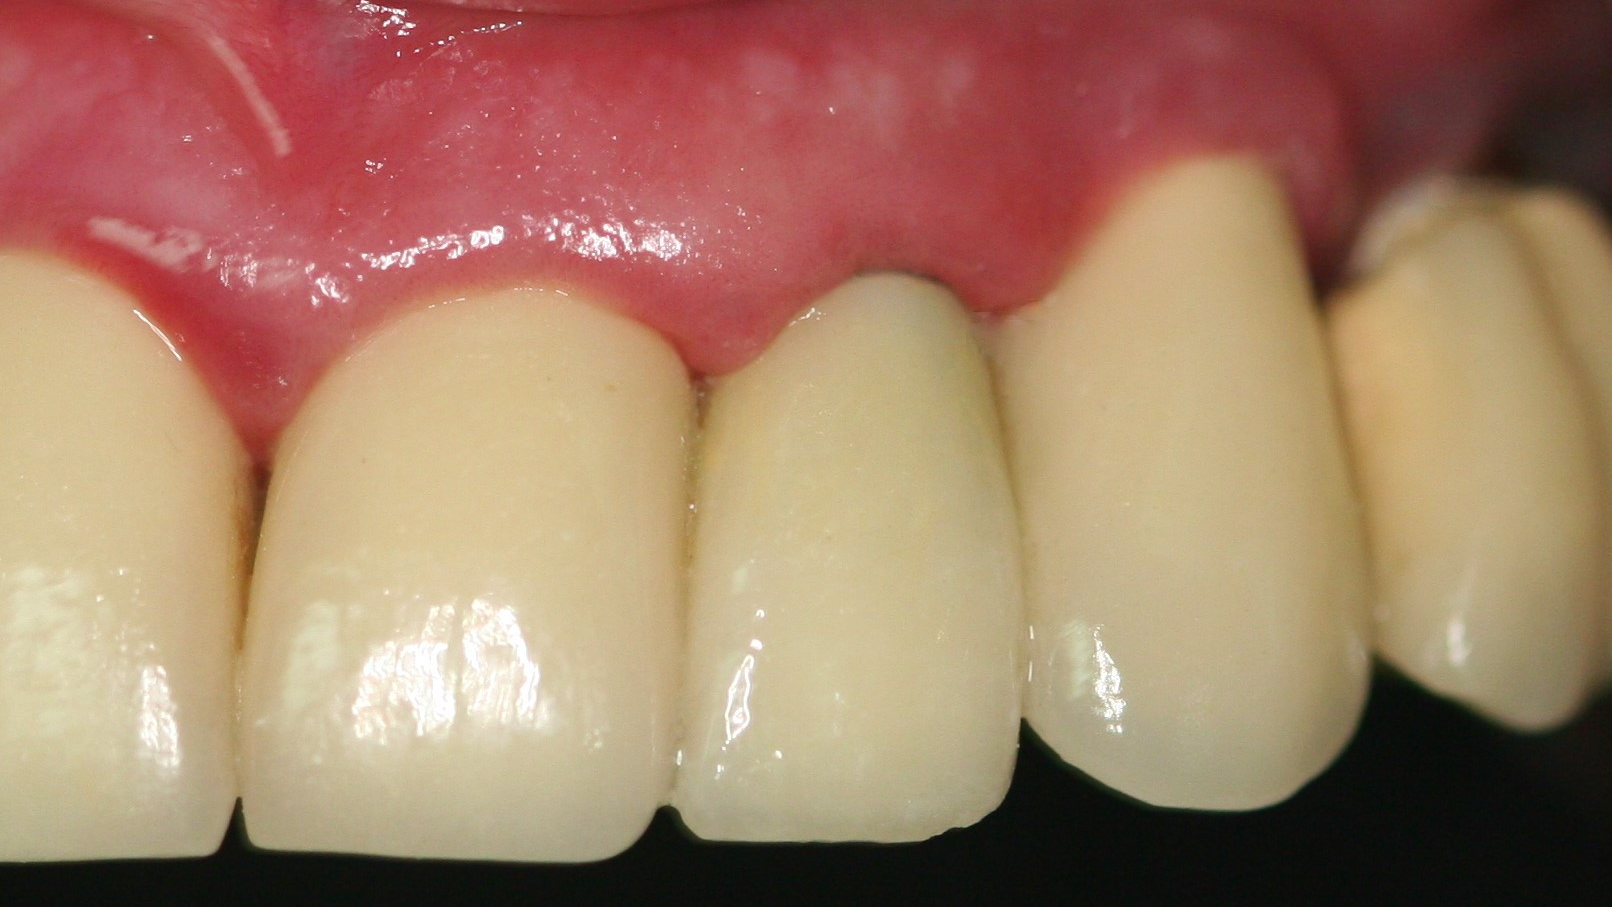

- Treatment plan: Extraction/immediate implant placement with nonfunctional provisional

- Implant: Ditron Ultimate 3.75 x 16 mm

- Abutment: Final straight 11.5 mm titanium abutment delivered at time of implant placement